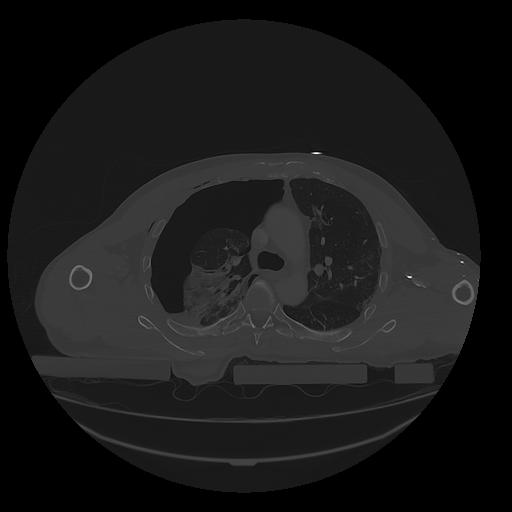

31 PULMON,CE,Vol,1.0,PULMON,,